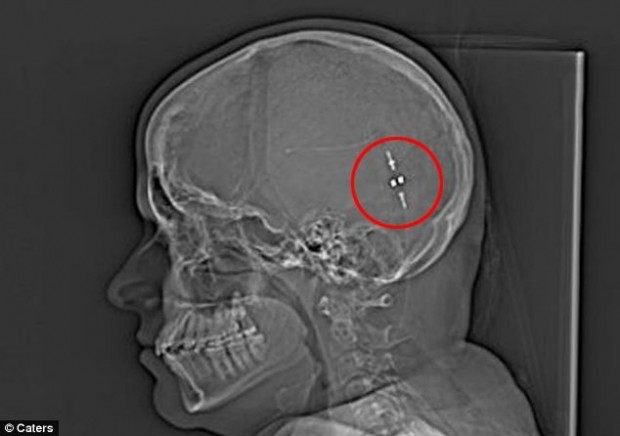

Но после того, как они нашли способ удалять избыток жидкости из ее мозга в желудок, ее жизнь изменилась. Слив, также известный, как желудочно-перитонеальный шунт, соединил мозг и желудок, позволяя ей переварить свою мозговую жидкость и снизить давление на мозг.Раньше моя жизнь была довольно жалкой. Я проводила дни напролет в постели и меня переполняла жалость к самой себе. Я не хотела жить, потому что у меня не было жизни, как таковой, а лишь жуткие головные боли. Я перепробовала множество лекарств, которые либо вообще не помогали, либо давали непродолжительный эффект, поэтому, когда мой врач посоветовала мне установить шунт, я ухватилась за эту возможность, — говорит Сэм.

И только в мае прошлого года девушке был установлен шунт для слива лишней жидкости. Сэм надеялась на немедленное облегчение, но ее мозгу потребовалось время, чтобы привыкнуть к инородному телу. Спустя некоторое время Сэм приспособилась к изменениям и с тех пор она снова живет нормальной жизнью.